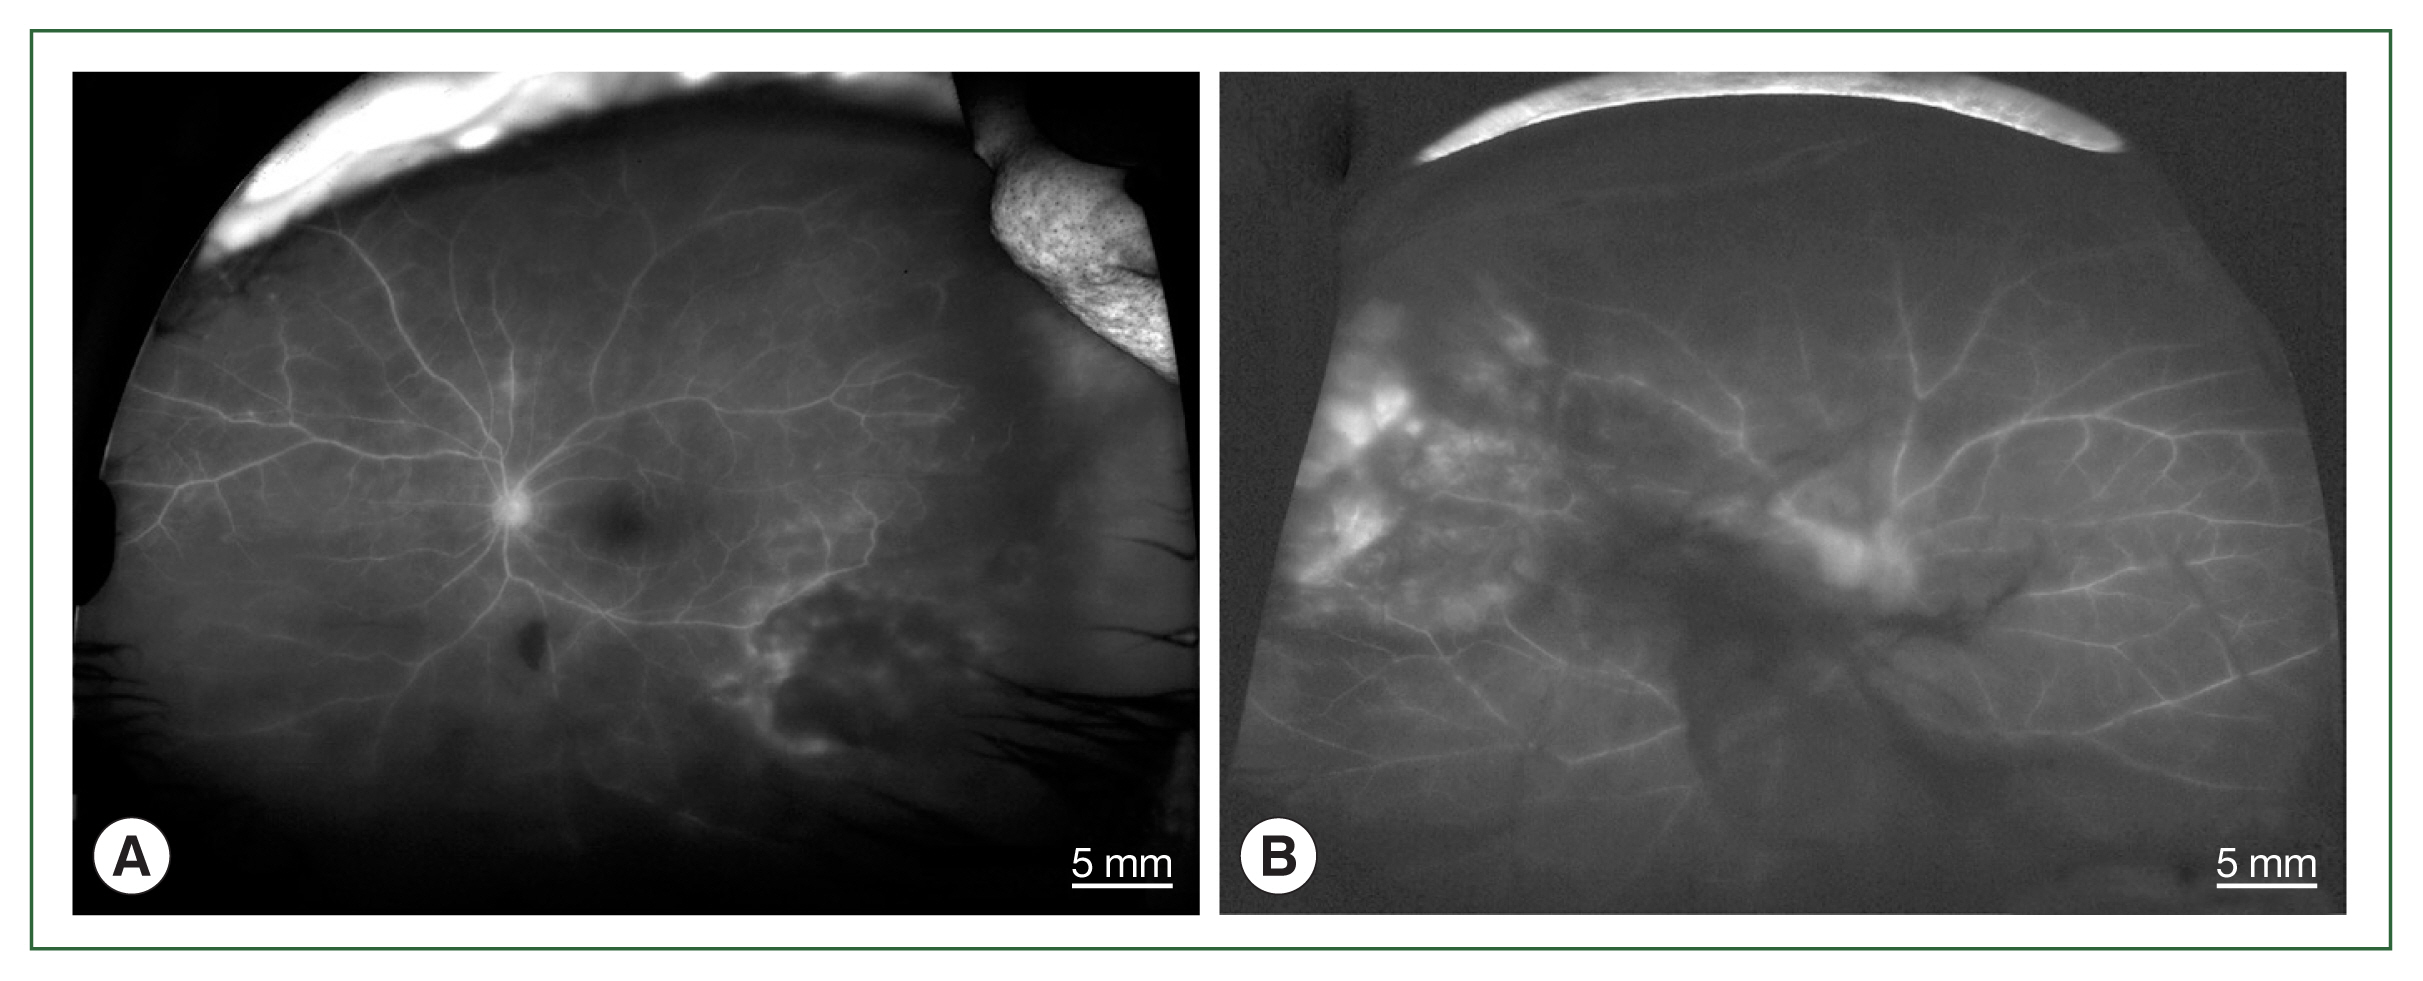

The 4 patients presented persistent unilateral visual disturbance 2–3 months before assessment. The ocular examination revealed that all study patients also exhibited unilateral panuveitis. Two patients (cases 1 and 2) did not show signs of chorioretinal scars, while the other 2 patients (cases 3 and 4) had preexisting scars on the retina and choroid. All of them showed an initial decimal visual acuity between 0.1 and 0.5. The ophthalmic analysis also revealed active retinochoroiditis in the 4 patients (Fig. 1) and papillitis and periphlebitis in cases 1 and 4, which were more evident by fundus fluorescein angiography (Fig. 2). All study patients also exhibited vitritis and anterior uveitis. Three patients (cases 1, 3, and 4) who underwent vitrectomy for diagnostic and therapeutic reasons had negative cytology for lymphoma cells. The remaining patient (case 3) had re-vitrectomy combined with scleral encircling for total retinal detachments developed later (Fig. 3). Only 1 patient (case 1), who was previously diagnosed with acute retinal necrosis (ARN) in a local ophthalmology clinic, received a systemic steroid treatment (60 mg per day) for posterior uveitis before visiting the Eye Center at the Seoul St. Mary Hospital, Catholic University. None had received any medication (including antibiotics) before the examination.